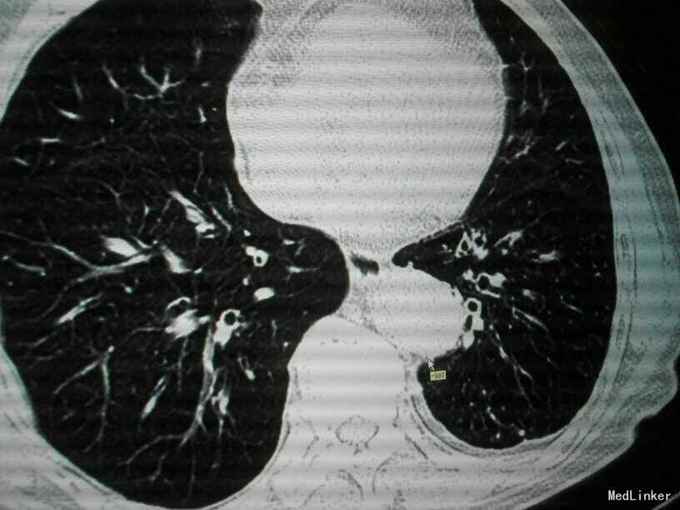

查体:唇指发绀,桶状胸,肋间隙增宽,双肺叩诊呈过清音,双肺呼吸音粗,可闻及散在干湿性啰音,未闻及明显湿性罗音,呼气延长,心腹阴性,双下肢轻度水肿。 辅助检查:入院后血气分析 PH 7.41 PCO2 43mmHg,PO2 73mmHg,BE 2.7mmol/L SO2:96%;心电图:室性早搏;胸片:符合慢支合并双肺炎症;肺CT示1.两肺多发支气管扩张并感染2.两肺间质纤维化,两侧胸膜增厚;心脏彩超:肺动脉压增高,肺动脉略宽;痰培养:肺炎克雷伯杆菌亚种;

诊断:慢阻肺急性发作;支气管扩张并感染;肺间质纤维化;慢性肺心病 治疗经过:抗炎:哌拉西林他唑巴坦;化痰:羧甲司坦口服液+盐酸氨溴索针;解痉平喘:多索茶碱,复方异丙托溴铵雾化溶液+布地奈德雾化混悬剂,雾化吸入;扩冠、减轻心脏负荷:硝酸甘油针;利尿:拖拉塞米针;3日后停硝酸甘油,改单硝酸异山梨酯缓释片口服,后患者出现胸闷、胸痛、气短症状加重,请心内科会诊后,给予呋塞米20㎎,隔日1次口服;螺内酯片20㎎,1日1次;替米沙坦片40㎎ 1日1次;美托洛尔6.25㎎;氯化钾缓释片 0.5g,1日2次;并给予抗血小板聚集、调脂、稳定斑块等治疗;治疗10天后,患者受凉后出现畏寒、发热,侧体温38.1℃,停哌拉西林他唑巴坦,改为盐酸莫西沙星针0.4g,1日1次,其余治疗同前;治疗3天后患者体温恢复正常,偶有咳嗽,咳少量白色黏痰,症状好转,出院。